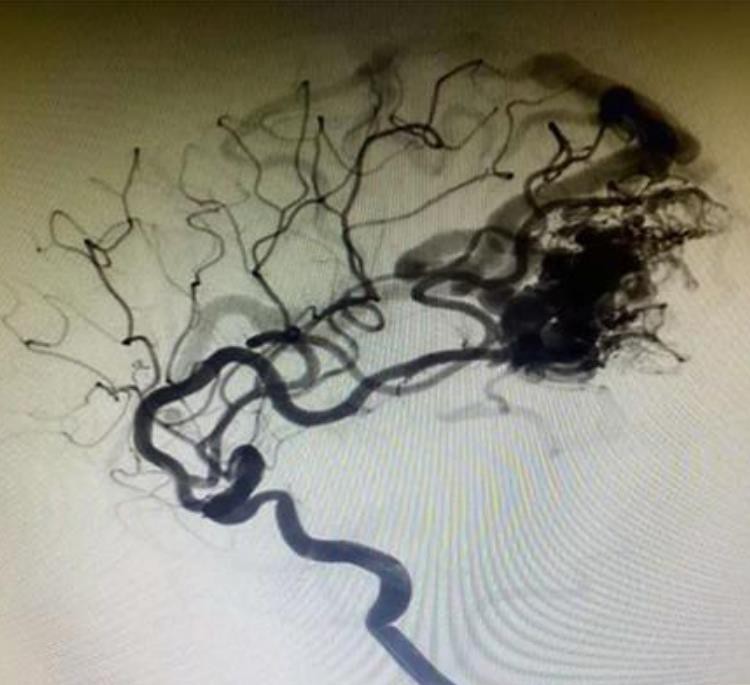

Lava -12 sistem embolik cecair intrakranial

Bila lavaTmIntracranial Aneurysms Cecair Embolic Systems dihubungi dengan darah atau sebarang larutan akueus, permukaannya akan segera mengukuhkan dan membentuk filem pelindung. DMSO dalam ejen embolik dicairkan dan tersebar di dalam darah, supaya serbuk tantalum dibalut oleh EvOH dicetuskan dan dikuatkan dari luar ke dalam. Pada masa yang sama, lava tersebar jauh di bawah tekanan suntikan. Akhirnya, ia membentuk badan embolik yang spongy pada kedudukan embolisasi.

LavaTmSistem embolisasi aneurisme diperbuat daripada bahan yang tidak melekat, jadi ia lebih selamat dan tidak melekat kateter.

Ia adalah formula kelikatan rendah yang unik dengan pelbagai model lava -12, lava -18 dan lava -34.

Ia mempunyai penyebaran dan penembusan yang lebih baik. Dan ia dapat menembusi luka, dan mencapai kapal distal.

Serbuk Tantalum lebih halus, lebih perlahan mendakan dan lebih jelas radiografi berbanding pesaing.